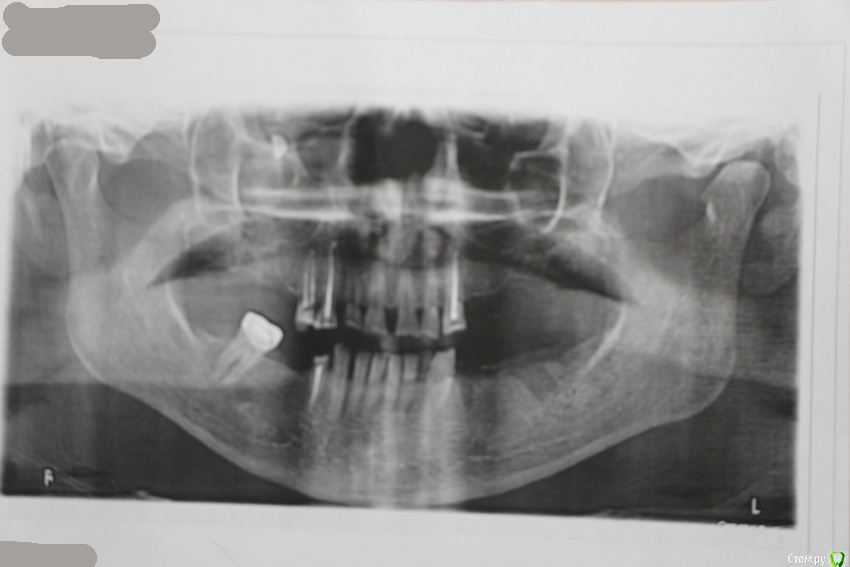

лелька1705 Опубликовано 24 января, 2015 Поделиться Опубликовано 24 января, 2015 (изменено) Одни врачи говорят без проблем имппланты, другие говорят, что никак не возможно, только съемный протез. Как бы понять, кто прав. Развейте сомнения, пожалуйста. Спасибо! Изменено 24 января, 2015 пользователем лелька1705 Ссылка на комментарий

diesel87 Опубликовано 25 января, 2015 Поделиться Опубликовано 25 января, 2015 Не вижу проблем по обеим челюстям, высота позволяет, надо смотреть на ширину, но и это вопрос решаемый, Ссылка на комментарий

лелька1705 Опубликовано 26 января, 2015 Автор Поделиться Опубликовано 26 января, 2015 (изменено) Верно то, что после илиВ том-то и дело, что врач мне нравится ))Пока поставлено три импланта, по-моему все хорошо. Затем планируется: коронки на передние верхние зубы, мост на нижней челюсти справа и съемный на верхней. Вопрос! После ношения съемного протеза, возможно будет установка имплантов? Все-равно нужно время, денег заработать Спасибо! Изменено 26 января, 2015 пользователем лелька1705 Ссылка на комментарий